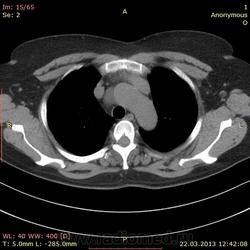

Пациентка 52 года. Поступила с жалобами на редкий сухой кашель, общую слабость, потливость, ощущение "лопания" в трахее, эпизодическое удушье. В ноябре 2012 перенесла двустороннюю полисегментарную пневмонию. Сейчас с подозрением на повторную пневомнию прислали на кт. В легких ничего особенного, а вот аорта меня заинтересовала.

Помогите с диф диагнозом. Думаю на расслоение аневризмы, но плотность этой штуки всего до 10 HU. Контрастирование не делаем, болюса нет((.

Пациентка 52 года. Поступила с жалобами на редкий сухой кашель, общую слабость, потливость, ощущение "лопания" в трахее, эпизодическое удушье. В ноябре 2012 перенесла двустороннюю полисегментарную пневмонию. Сейчас с подозрением на повторную пневомнию прислали на кт. В легких ничего особенного, а вот аорта меня заинтересовала.

Помогите с диф диагнозом. Думаю на расслоение аневризмы, но плотность этой штуки всего до 10 HU. Контрастирвоание не делаем, болюса нет((.

Ну, оценка аорты без контрастирования - это очень круто, но я бы отметил вероятность тромбированной аневризмы.

Про контраст я сама все понимаю(((( написала пока просто аневризма, ибо на декабрьских снимках эта штука тоже есть, и врач тогда не акцентировал внимание. В понедельник, думаю эхо делать будут...

Сделали узи. Никакого намека на аневризму. Видимо киста такая.

без контраста по первому же кадру ясно, что это целомическая киста перикарда, классическое расположение и форма.